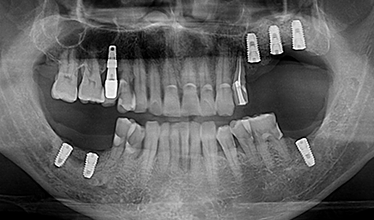

CASE 02

-

임플란트 식립 전 -

임플란트 식립 후 -

임플란트 보철 후